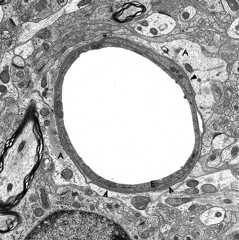

Unlike other organs and tissues, theendothelial cells that line brain capillaries have no fenestrations or pinocytotic (transportation) vesicles and havetightand adherens junctions that almost fuse adjacent endothelial cells. Moreover, these endothelial cells have different receptors and ion channels on their surface facing the lumen than on the surfaces facing the brain, an arrangement that facilitates transcellular transport. This anatomy is the basis of theblood-brainbarrier (BBB). The endothelial cells are surrounded by abasement membrane made up of collagens, laminins, and proteoglycans. A discontinuous layer of pericytes are embedded in this basement membrane.Astrocytic processes rich in Aquaporin 4 (AQP4) cover the capillaries. The space between them and the capillary basement membrane contains a few perivascular macrophages and rare lymphocytes that cross the BBB (passing through endothelial cells rather than between them) and survey this space. The same types of cells are present in the perivascular (Virchow-Robin) space (see below). Brain endothelial cells do not express leukocyte adhesion molecules (LAMs) on their luminal surface and this limits the entry of leukocytes into brain tissue. In non-diseased states, no immune cells or molecules are found deeper in brain interstitial space, resulting in an “immune privileged” status. During development, astrocytes induce brain endothelial cells to develop in this special leak-proof fashion.

The BBB separates plasma from the interstitial space of the CNS and is key to maintaining homeostasis in the CNS. It controls the traffic of molecules, including ions and water in and out of the brain and plays an important role in supplying the brain with nutrients and getting rid of waste and toxic products. The ability to exclude certain substances from brain interstitial space has to do not only with the vascular anatomy, but also with lipid solubility and selective transcellular transport by endothelial cells. Lipophilic compounds cross the BBB easier than hydrophilic ones do, and small lipophilic molecules such as O2 and CO2 diffuse freely. Hydrophilic substances can only get across brain capillaries through endothelial cells rather than between them. Some hydrophilic molecules, including glucose and amino acids, enter endothelial cells with the help of transporters, and larger molecules, including proteins, enter via receptor-mediated endocytosis and exit along the opposite surface by exocytosis. GLUT1 is the glucose transporter. The ATP-binding cassette (ABC) transporters are important for transport of lipophilic substances and efflux of toxic metabolites. The BBB protects the brain from toxic substances but also impedes the entry of drugs. Circulating leukocytes enter the brain by passing through endothelial cells rather than between them. Astrocytes cover almost the entire surface of brain capillaries; they are interposed between the vasculature and neurons thus linking neuronal activity to BBB function. Hypertonic stimuli and chemical substances including glutamate and certain cytokines can open the BBB. Astrocytic processes express Aquaporin 4, another water channel that facilitates transport of water.

The major cerebral arteries and veins traverse the subarachnoid space and penetrate into the brain, where they branch into smaller vessels and eventually capillaries. Capillaries are in contact with astrocytic processes. Vessels larger than capillaries are separated from the surrounding brain tissue by a space (theperivascular or Virchow-Robin space), which is an extension of the subarachnoid space. The perivascular space is a component of the“glymphatic”-glial lymphatic- system (analogous to the lymphatic system of the body) which facilitates exchange of molecules between the CSF and the ISF of the brain. CSF flows into brain tissue at the periarterial space, mixes with ISF in brain tissue and effluxes from brain tissue into the CSF along perivenous spaces. It is thought that cardiac pulsations facilitate the exchange of substances between the ISF and the CSF. The glymphatic system helps rid the brain of waste products and maintains homeostasis. Such products include beta-amyloid and tau protein. Thus, the glymphatic system may be important in the pathogenesis of Alzheimer’s disease and chronic traumatic encephalopathy.

The outer surface of thisperivascular space (PVS) is formed by the glia limitans.The inner surface is the vascular basement membrane.Postcapillary venules are also surrounded by a PVS. The PVS that surrounds postcapillaryvenules is the portal of entry of leukocytesinto the brain in the normal state and during inflammation.Circulating monocytes and lymphocytes normally traversepostcapillary venules and enter the PVS. In the courseof inflammation, such as MS, this entry is increasedbecause of leukocyte interactions with inflamed endothelialcells. Furthermore, leukocytes penetrate the glialimitans and enter into the CNS. The latter move isfacilitated by matrix metalloproteinases (MMPs) producedby macrophages, which loosen the glia limitans.